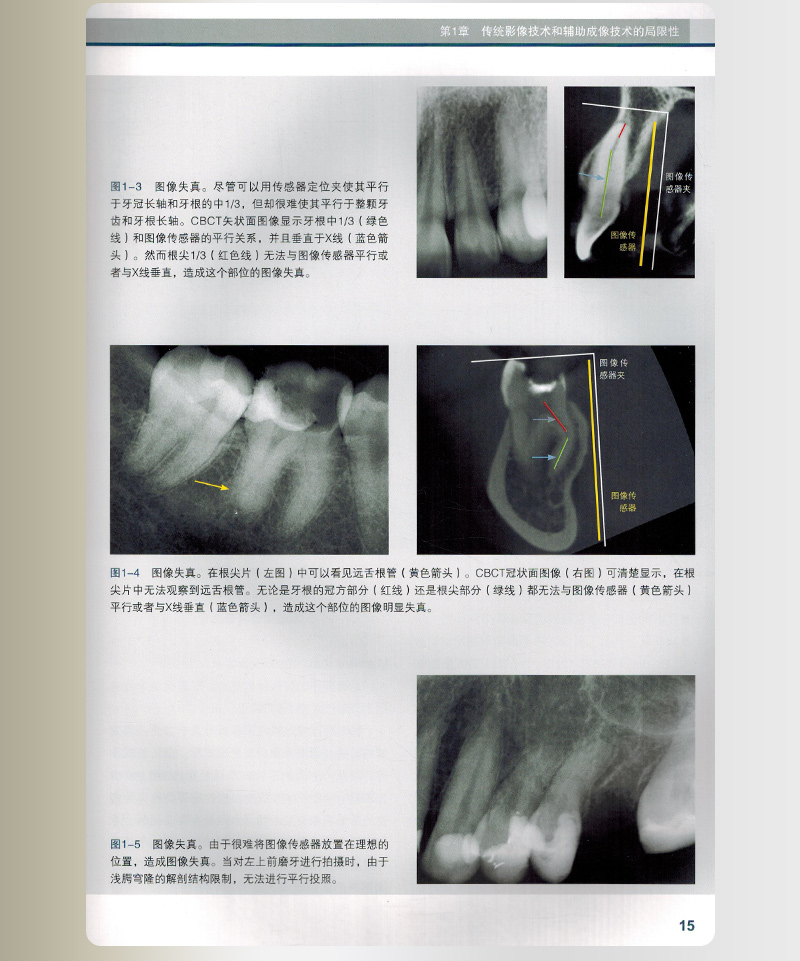

影像失真